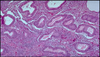

normal breast histo

22

Q

A

acute mastitis

23

Q

A

Fat necrosis

24

Q

A

epitheleal hyperplasia